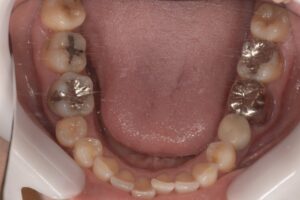

最終的なセラミックを装着した状態です。

骨の状態や周囲の歯との移行性など問題なく、キレイに作製することができました。

何も違和感なく、自分の歯と同じように噛めると喜んでいただけました。